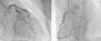

Angiography revealed absence of obstructive coronary disease or acute plaque rupture (Figure 1). Ventriculography showed apical and midventricular dysfunction with hyperkinesis of the basal myocardial segments and severely depressed ejection fraction (Figure 2). A second detailed transthoracic echocardiographic examination confirmed apical akinesis, basal hyperkinesis and severe systolic left ventricular (LV) dysfunction; apical ballooning syndrome was confirmed.